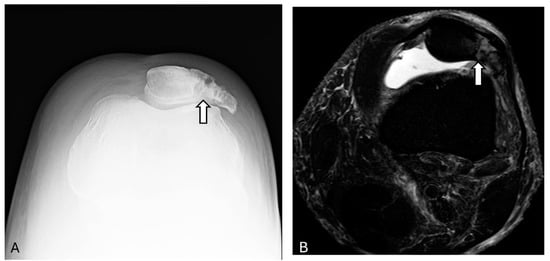

3.8. Prepatellar Bursitis